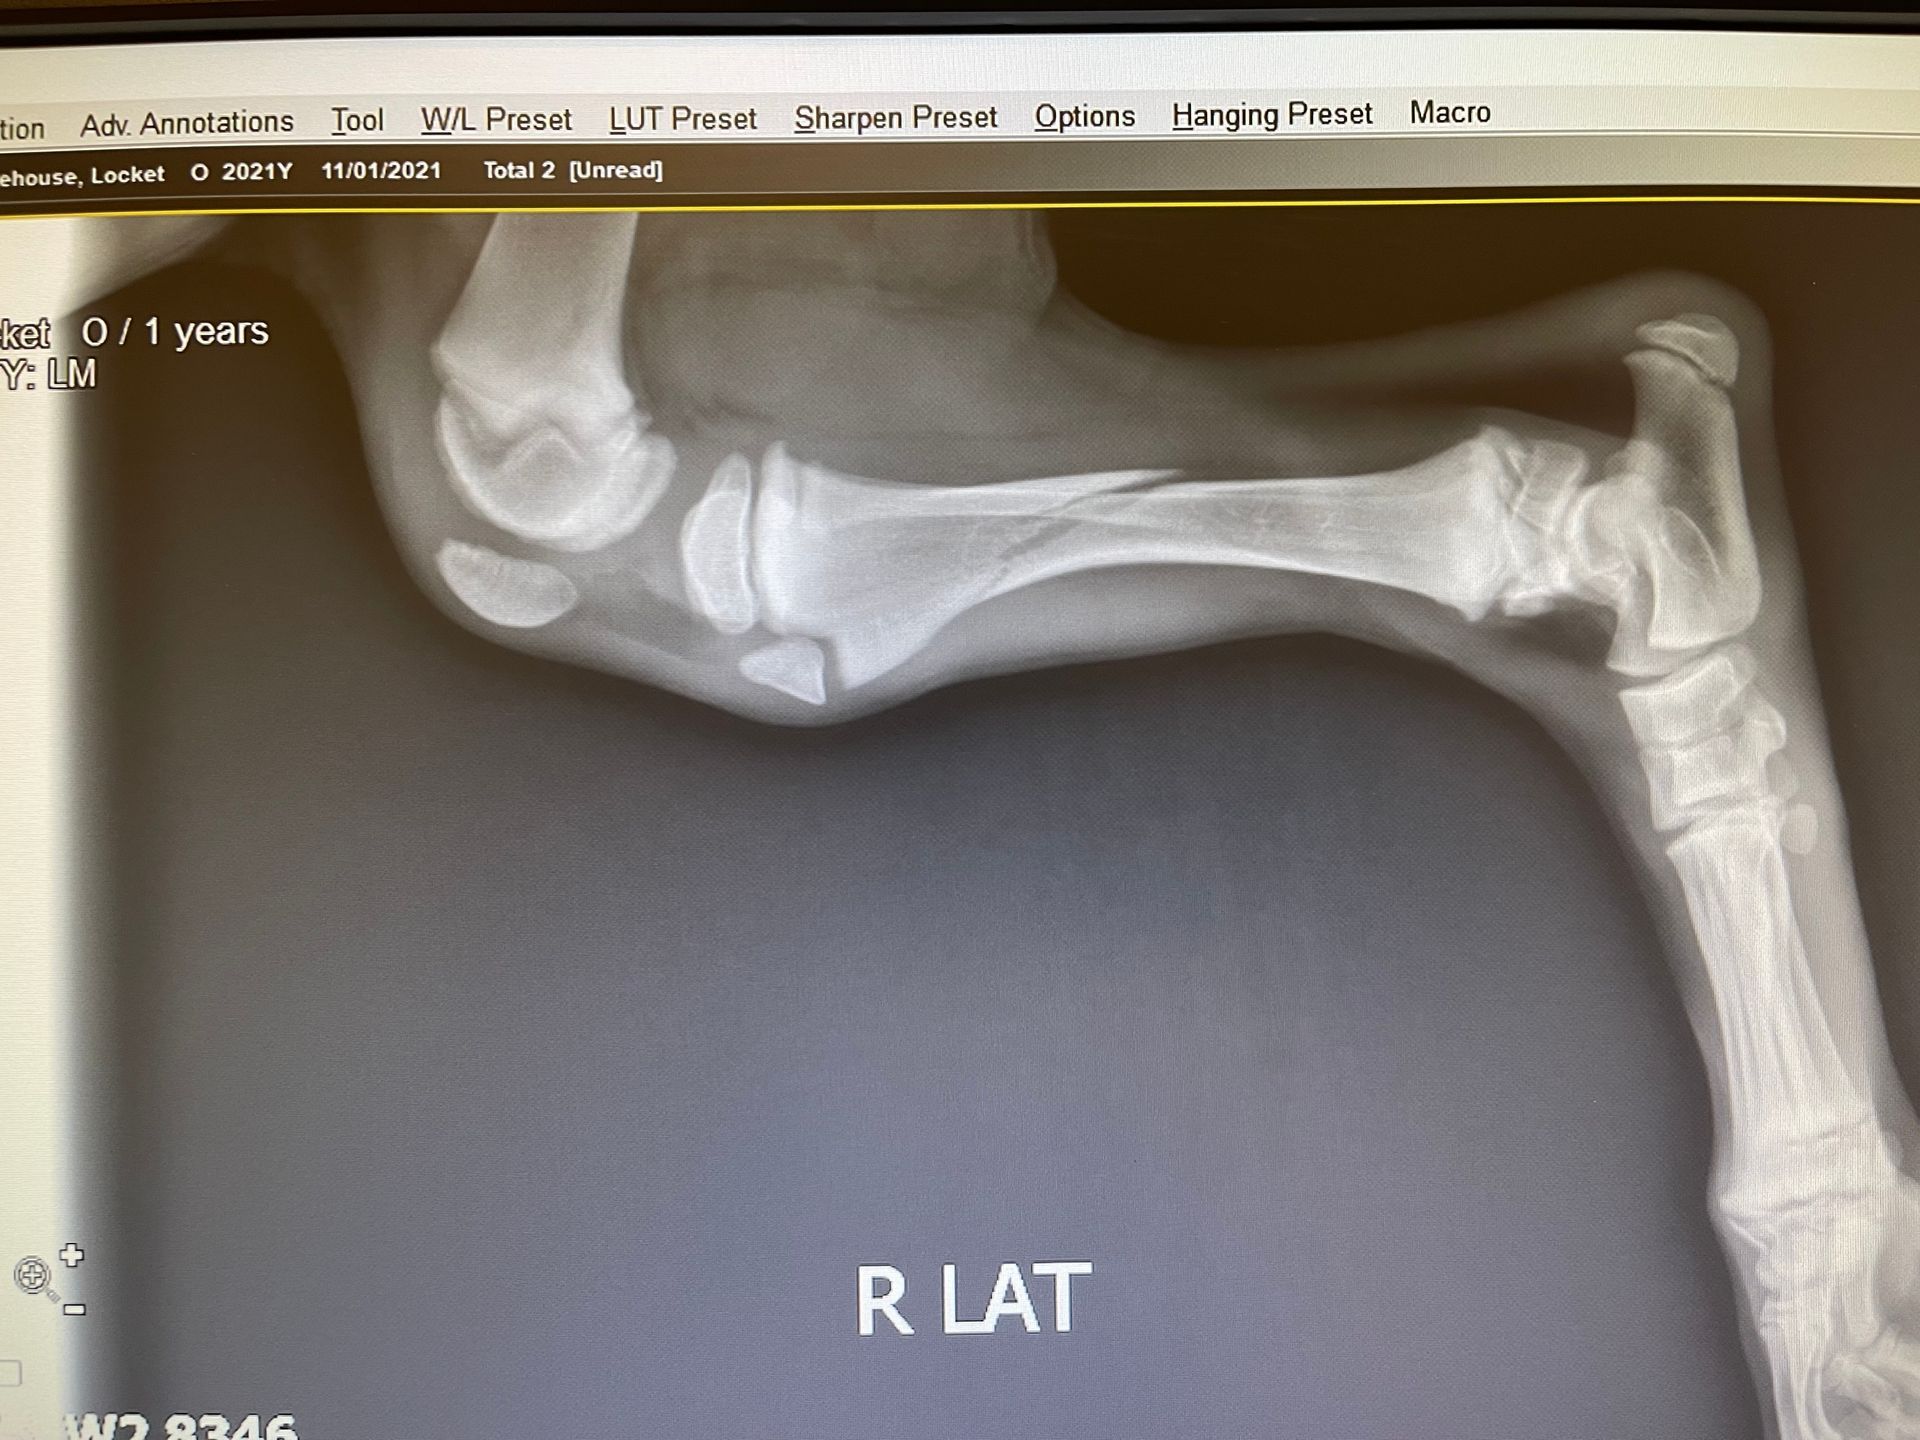

TRANSPARENCY is important! Our beloved Locket unfortunately broke her Right rear leg at 11 weeks of age on 11/1/2021. She was in a cast to her hip for over 6 weeks, on restricted activity several weeks more, and went through months of physical therapy. She recovered well enough to earn her Championship (winning both of her specialty majors on movement) and has continued to participate in lots of fun activities. Unfortunately, as is often the case with injuries like this, her hip joint was affected and there have been changes to the femoral head over time. OFA classified her as Mild UR (Mild Unilateral Right). We knew this was likely and we submitted her X Rays to OFA anyway (and checked the box!!)- both in the interest of transparency & education. For that reason we will also share photos & X Rays below.